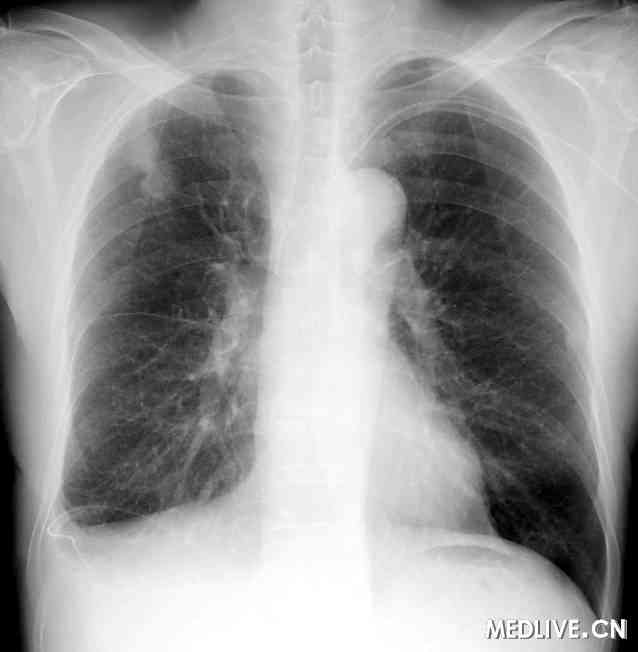

经过2个周期的卡铂+吉西他滨化疗,原发肿瘤和转移淋巴结仍快速进展,并发生乳糜胸和乳糜心包(见图1)。每日从2个腔中引流出1,500~3,000 ml的乳糜液。鉴于心包引流液中的甘油三酯水平始终高于胸膜腔引流液,初步诊断为原发乳糜心包继发乳糜胸。反复对乳糜液行细胞学检查,结果均未发现癌细胞。虽然经静脉输入营养液和反复行胸膜固定术,但乳糜心包和乳糜胸均得不到控制。我们尝试切开左侧胸廓而直接结扎胸导管,但术中未能找到渗漏部位,只好对胸导管周围行大范围结扎。术后,乳糜液引流量逐渐降至每日1,500~2,000 ml,但在2周内逐渐恢复至术前水平。虽然患者的总体情况相对较好,但其生活质量因长期持续胸导管引流而明显下降。

胸片显示右侧胸腔和心包腔大量渗出